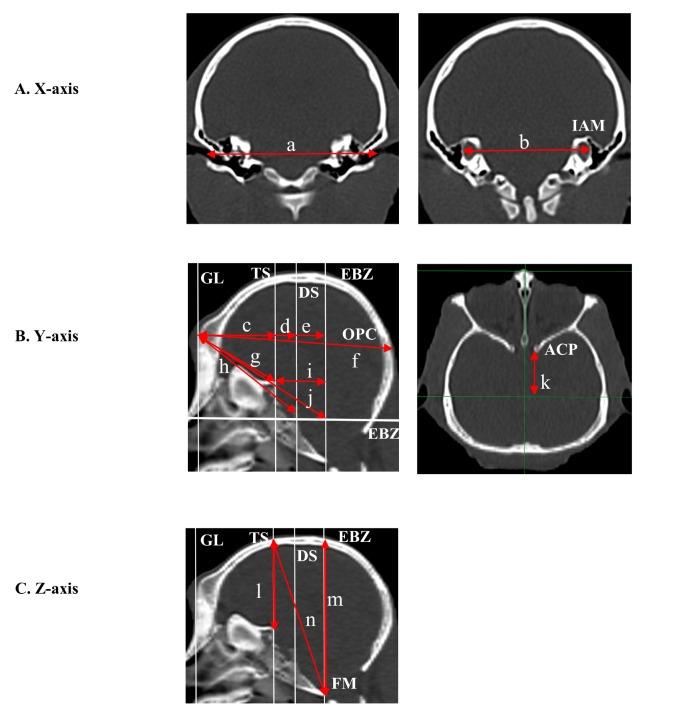

The brain grows with age in non-human primates (NHPs). Therefore, atlas-based stereotactic coordinates cannot be used directly to target subcortical structures if the size of the animal's brain differs from that used in the stereotactic atlas. Furthermore, growth is non-uniform across different cortical regions, making it difficult to simply apply a single brain-expansion ratio. We determined the skull reference lines that best reflect changes in brain size along the , , and axes and plotted the changes in reference-line length against the changes in body weight. The skull reference lines had a linear relationship with body weight. However, comparison of skull reference lines with body weight confirmed the non-uniform skull growth during postnatal development, with skull growth more prominent in the and axes than the axis. Comparing the differences between the atlas-based lengths and those calculated empirically from plot-based linear fits, we created craniometric indices that can be used to modify stereotactic coordinates along all axes. We verified the accuracy of the corrected stereotactic targeting by infusing dye into internal capsule in euthanized and preserved NHP brains. Our axis-specific, craniometric-index-adjusted stereotactic targeting enabled us to correct for targeting errors arising from differences in brain size. Histological verification showed that the method was accurate to within 1 mm. Craniometric index-adjusted targeting is a simple and relatively accurate method that can be used for NHP stereotactic surgery in the general laboratory, without the need for high-resolution imaging.

在非人灵长类动物(NHPs)中,大脑会随着年龄增长。因此,如果动物大脑的大小与立体定向图谱中使用的大脑大小不同,基于图谱的立体定向坐标就不能直接用于靶向皮层下结构。此外,不同皮层区域的生长并不均匀,这使得简单应用单一的大脑扩张率变得困难。我们确定了能最好地反映大脑大小沿x、y和z轴变化的颅骨参考线,并绘制了参考线长度变化与体重变化的关系图。颅骨参考线与体重呈线性关系。然而,将颅骨参考线与体重进行比较证实了出生后发育过程中颅骨生长的不均匀性,颅骨在x和y轴上的生长比z轴更显著。通过比较基于图谱的长度与根据基于绘图的线性拟合经验计算出的长度之间的差异,我们创建了颅骨测量指数,可用于沿所有轴修改立体定向坐标。我们通过向安乐死并保存的NHP大脑的内囊中注入染料,验证了校正后的立体定向靶向的准确性。我们基于轴特异性、经颅骨测量指数调整的立体定向靶向能够校正因大脑大小差异而产生的靶向误差。组织学验证表明该方法的准确性在1毫米以内。经颅骨测量指数调整的靶向是一种简单且相对准确的方法,可用于一般实验室中的NHP立体定向手术,无需高分辨率成像。